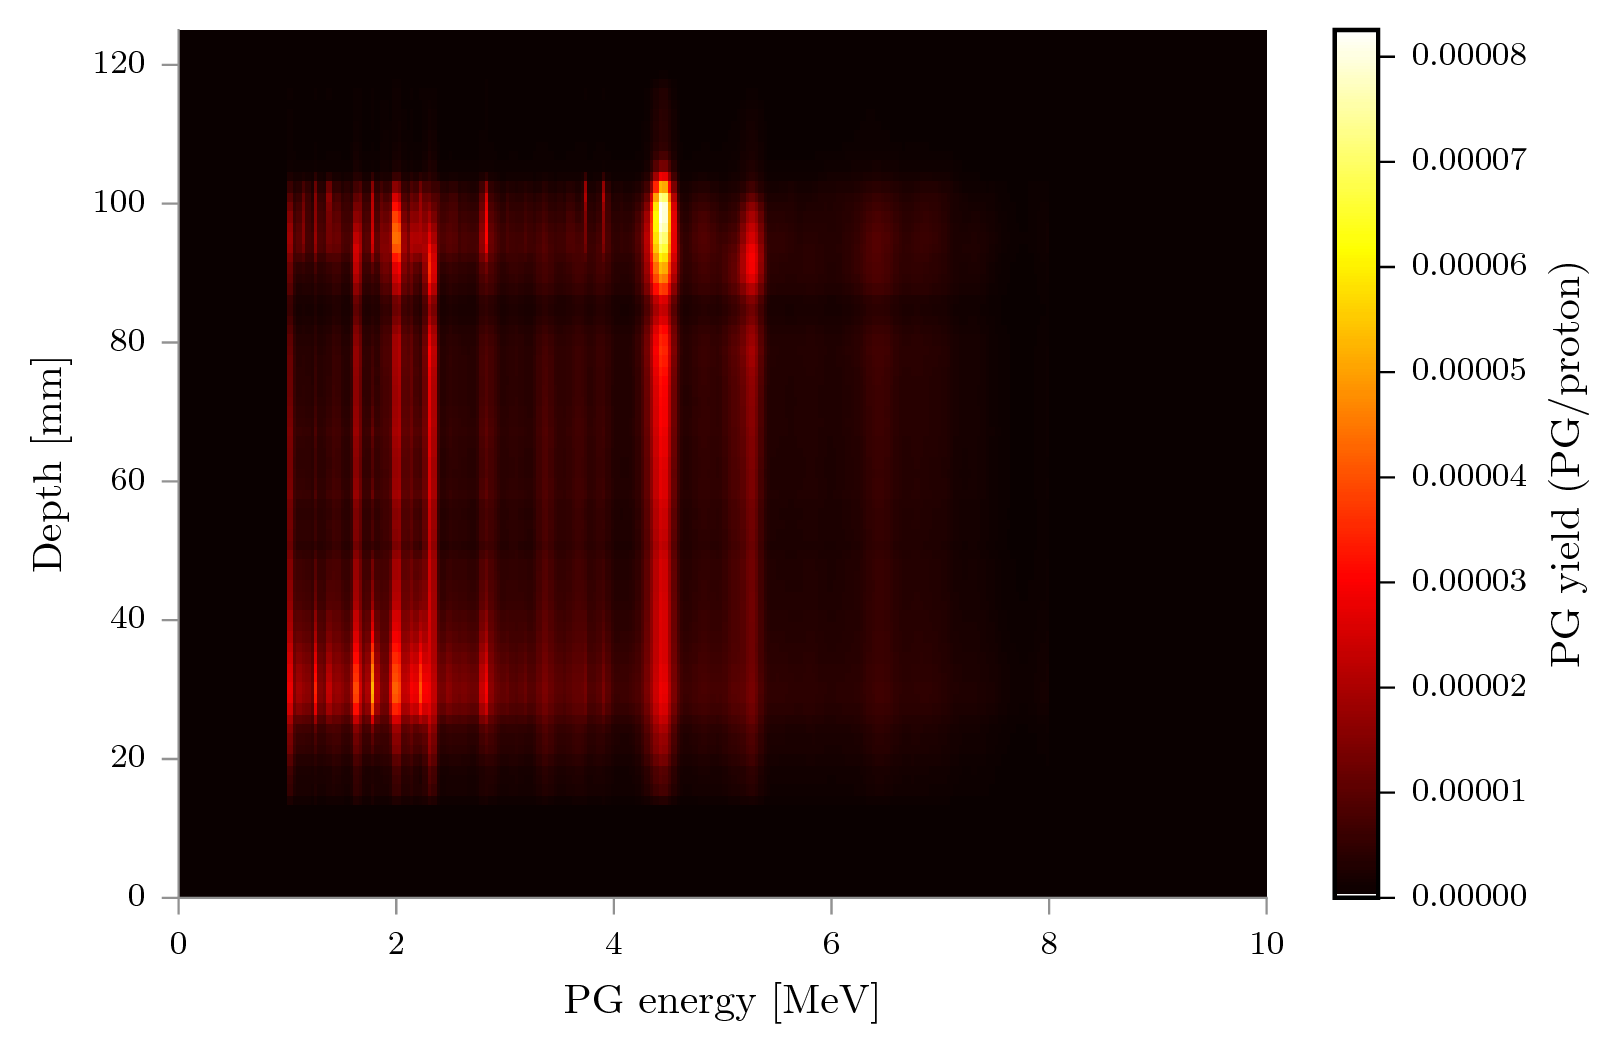

Test case 2: PG spectra as function of depth.

As far as the authors of this paper could establish, the only other published variance reduction technique for PGs is described in Sterpin et al. (2015). This method is fully analytic, incorporating experimental or pretabulated PG emission data and a model that assumes the PG emission region can be modeled similar to the dose in pencil beams. The method raytraces the materials touched by a pencil beam spot, and computes the expected 1D PG profile by a weighted sum of pregenerated profiles per material, which takes 0.3 to 10 seconds. The authors admit that this approach does not deal very well with lateral inhomogeneity, a problem that vpgTLE does not have due to TLE methods in principle being assumption free. Another benefit of vpgTLE is the shape of its output: a 4D image where for each voxel a PG spectrum is recorded. This permits the incorporation of the method in many different kinds of PG detector simulations, not just detectors that measure the range. As a small example, vpgTLE can be used to investigate the origin of the global spectrum as function of depth along the beam path in figure 11. vpgTLE will work with any collimated or Compton camera design, PG spectroscopy, or any future detector that takes advantage of spatial or spectral components. Moreover, vpgTLE does not assume anything about the proton flux: it uses Stage 1 to estimate it. The difficulty estimating PG yields due to beam spots that produce different ranges due to lateral inhomogeneity is therefore avoided: vpgTLE is as sensitive to inhomogeneity as regular MC.